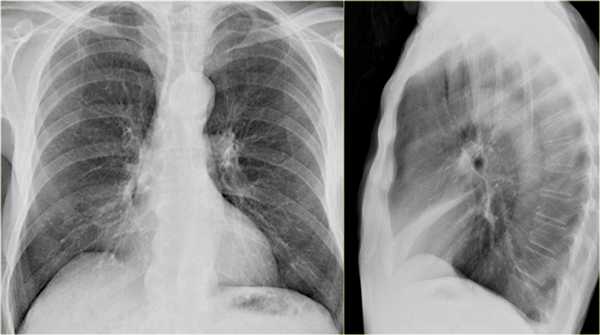

Ателектаз средней доли правого легкого.

- Симптом силуэта — нечеткие границы правых отделов сердца.

- Трехгранные изменения высокой плотности, визуализирующиеся на боковой рентгенограмме, являются результатом ателектаза средней доли правого легкого.

При ателектазе средней доли правого легкого подъем диафрагмы навсегда значительно выражен.